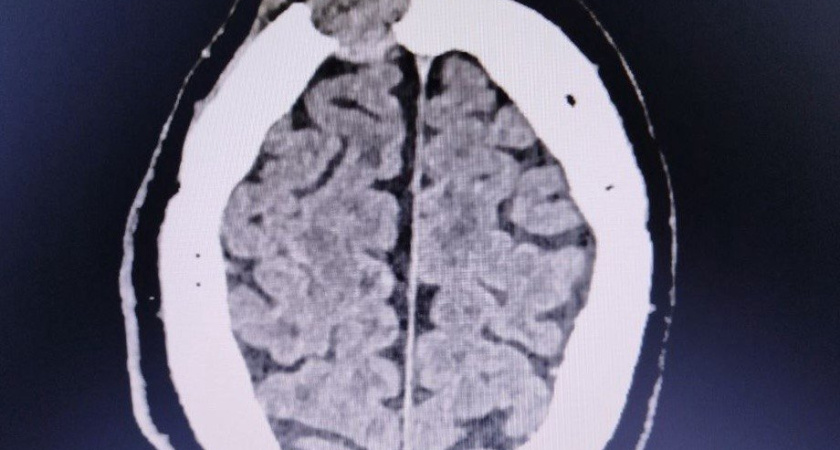

Для точной диагностики врачи провели компьютерную томографию. Результаты оказались неожиданными: на месте шишки обнаружилась опухоль, которая уже начала разрушать лобную кость. Пациента немедленно направили в нейрохирургическое отделение.